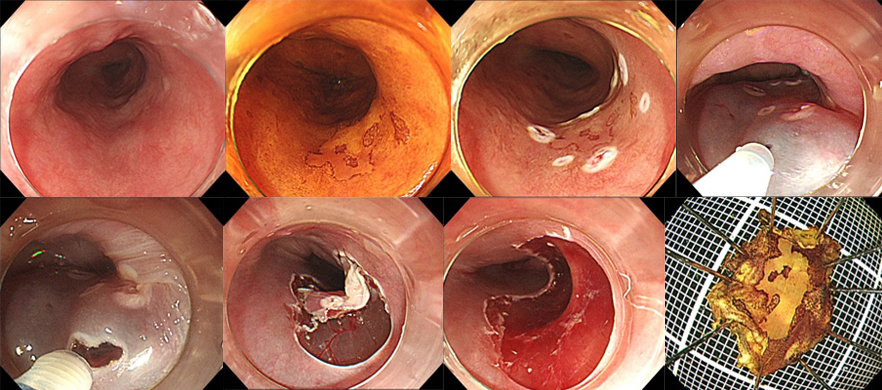

内視鏡と専用のナイフを用いて粘膜下で剥ぎ取る治療法です。大きな病変でも早期癌であれば確実に切除することが出来ます。当院では2003年より導入し多くの症例で非常に良好な成績をおさめています。食道・胃・十二指腸・大腸で治療可能です。